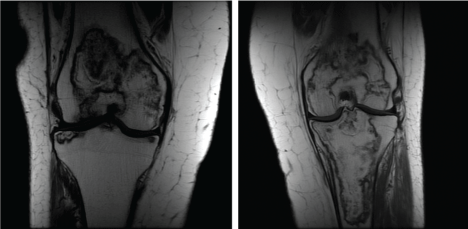

Given her history an MRI of the pelvis was done at that time showing bilateral femoral head osteonecrosis. Both femora had extensive involvement with collapse Figure 7 and Figure 8.

Figure 7: Preoperative coronal MRI. View Figure 7

Figure 8: Preoperative coronal and sagittal MRI of left hip. View Figure 8